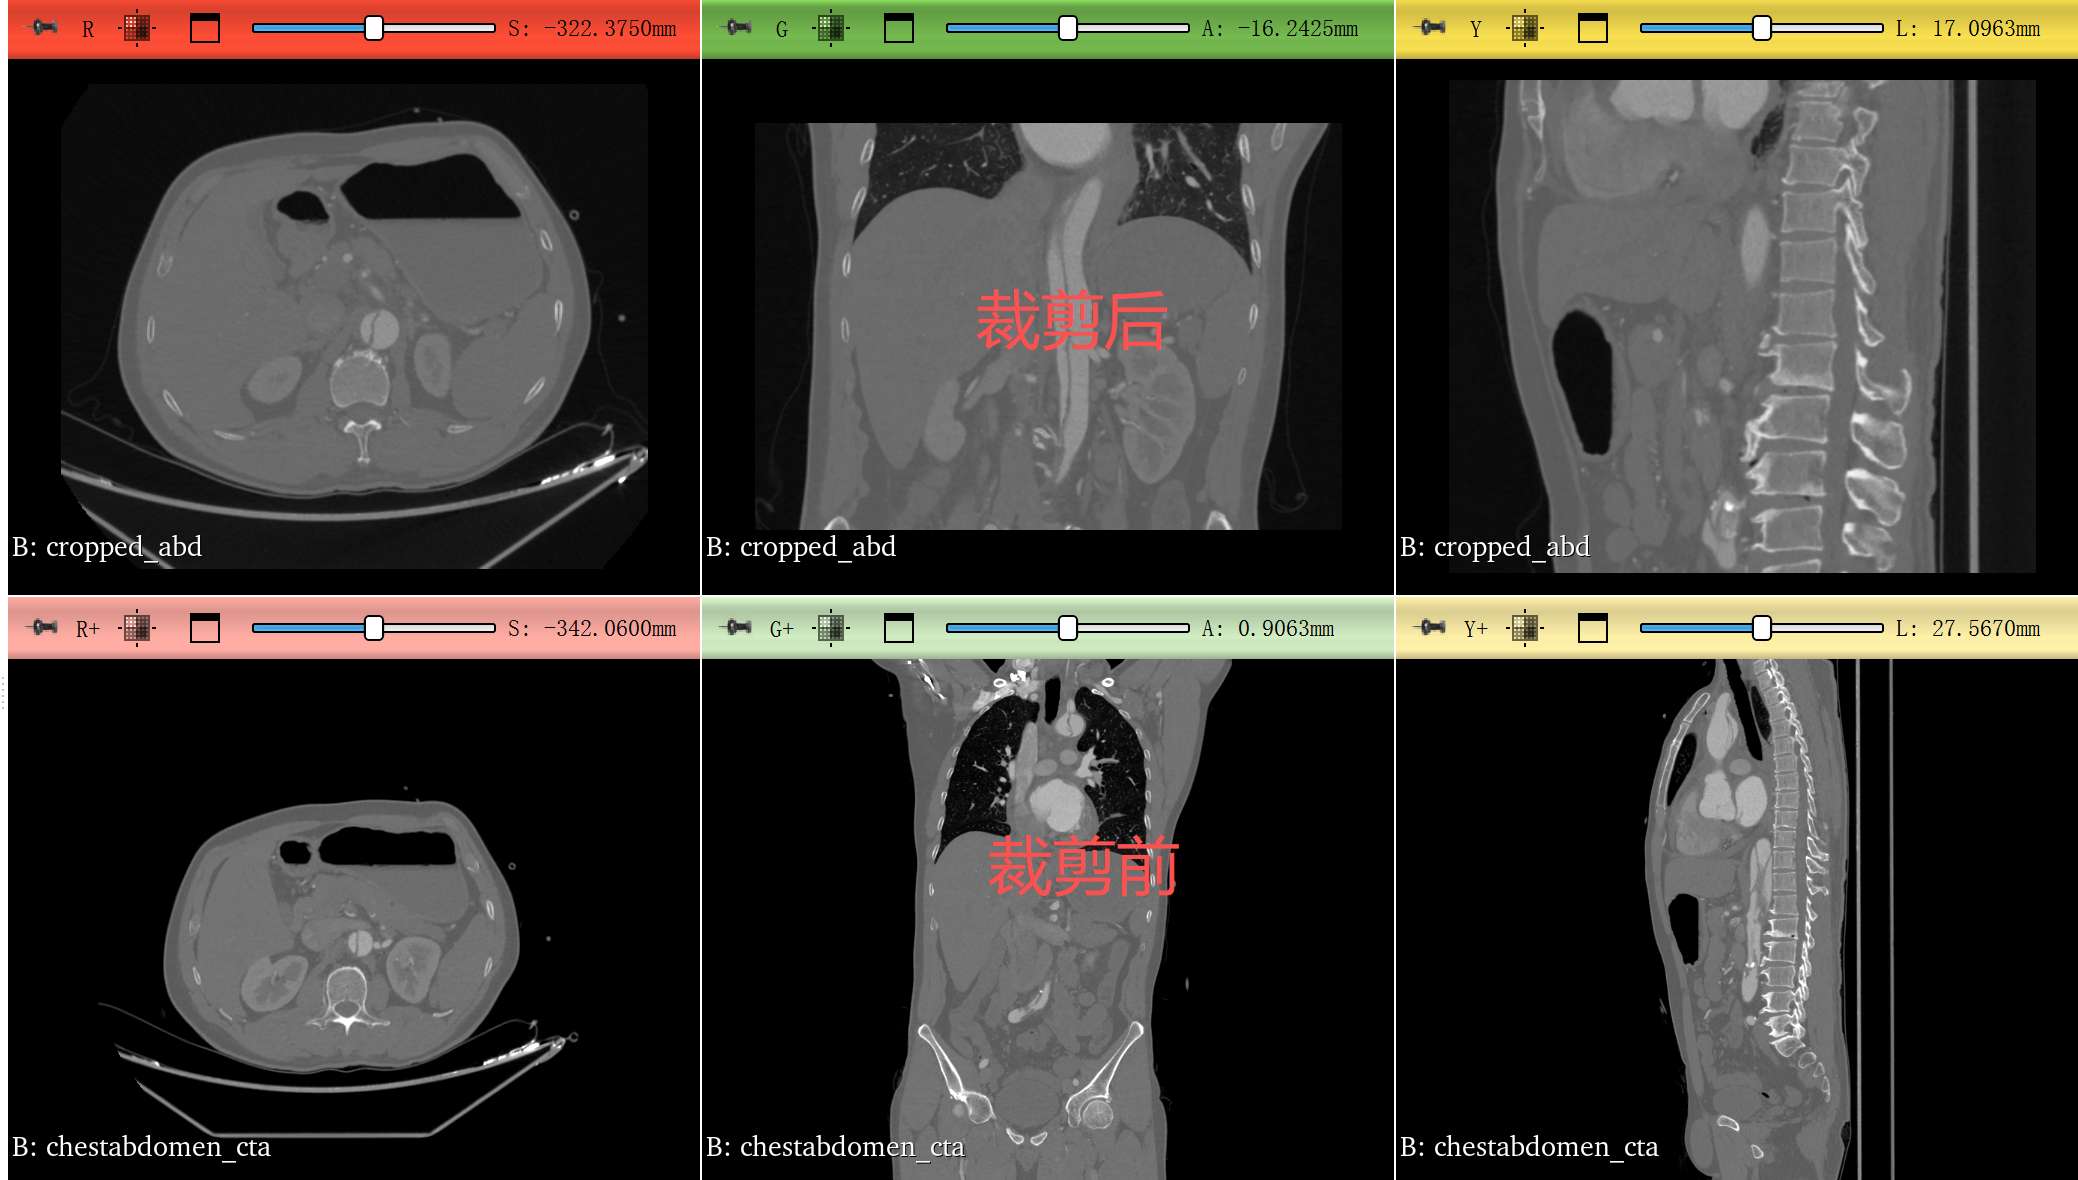

按图中所示,就裁剪好了。可以回到DATA模块进行保存数据。

该区域用于查看体数据的基本信息,通常是只读的。可以读取裁剪前裁剪后的图像大小以及分辨率

从这个图可以看到,我们裁剪只是改变了图像的大小,图像的分辨率是没有改变的。